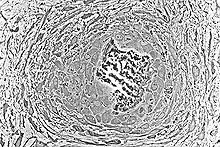

خلايا اللحمة المتوسطة الامبريولوجية (MSC) تتحول الي طبقات بدائية من الأنسجة الضامة الوعائية. بعض خلايا اللحمة المتوسطة تتحد مع بعضها عادة بالقرب من أو حول الاوعية الدموية، حيث تتمايز الي خلايا مكونة للعظم، وتترسب بدورها بالتتابع في المصفوفة. تسمي هذه التجمعات من المصفوفة العظمية شويكات العظم. خلايا اللحمة المتوسطة المتفرقة تتمايز الي بانيات العظم حيث تتراص علي طول سطح الشوكة، وتفرز المزيد من العظماني ، حيث تزيد حجم الشوكة.

كلما استمرت الأشواك في النمو، كلما التحمت الأشواك مع المجاورة لها وهذا يؤدي الي تكوين الترابيق.عندما يتم حجز بانيات العظم في المصفوفة، سوف تتحول الي خلايا عظمية .بانيات العظم تستمر في التراصّ فوق بعضها علي السطح كي تزيد من الحجم. كلما استمر النمو، الترابيق تصبح مترابطة وتكون منسوجة العظام. مصطلح الاسفنجي البدائي تستخدم ايضا للإشارة الي شبكة تربيقية أولية.